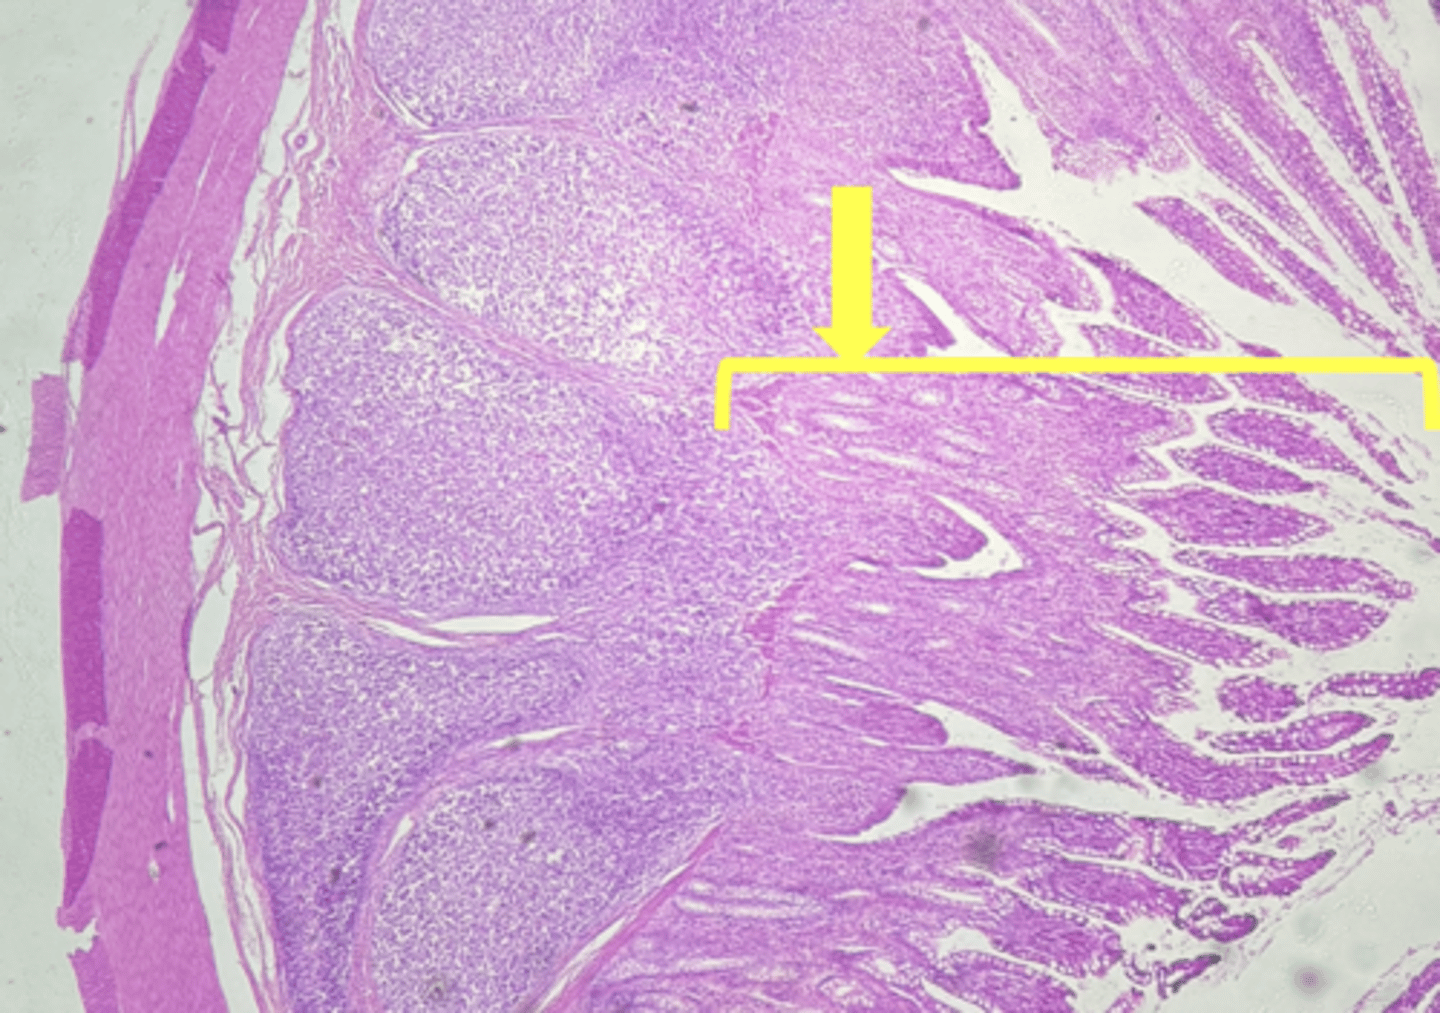

Duodenum (small intestine-cross section)

name the tissue

mucosa

myscularis externa

(duodenum)

Submucosa

Brunner's glands (KEY CHARACTERISTIC)

circular layer

longitudinal layer

Villi (KEY CHARACTERISTIC)

simple columnar epithelium

type of cell

intestinal crypts

lamina propria

muscularis mucosa